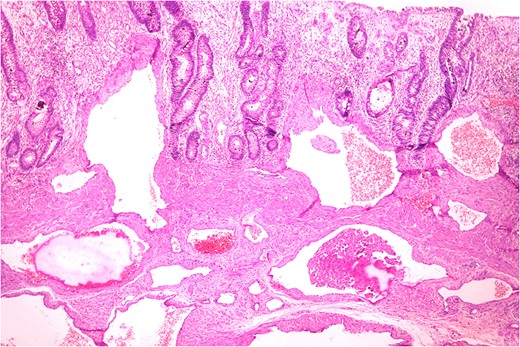

Markedly edematous and thickened mucosa due to vascular malformation.

Thickened wall with tiny cystic spaces in mucosa, muscularis propria and serosa of the wall (inset: histopathological picture of the same area).

Histopathologically diagnosis of Cavernous Vascular Malformation—Diffuse infiltrating (expansive) type was given.